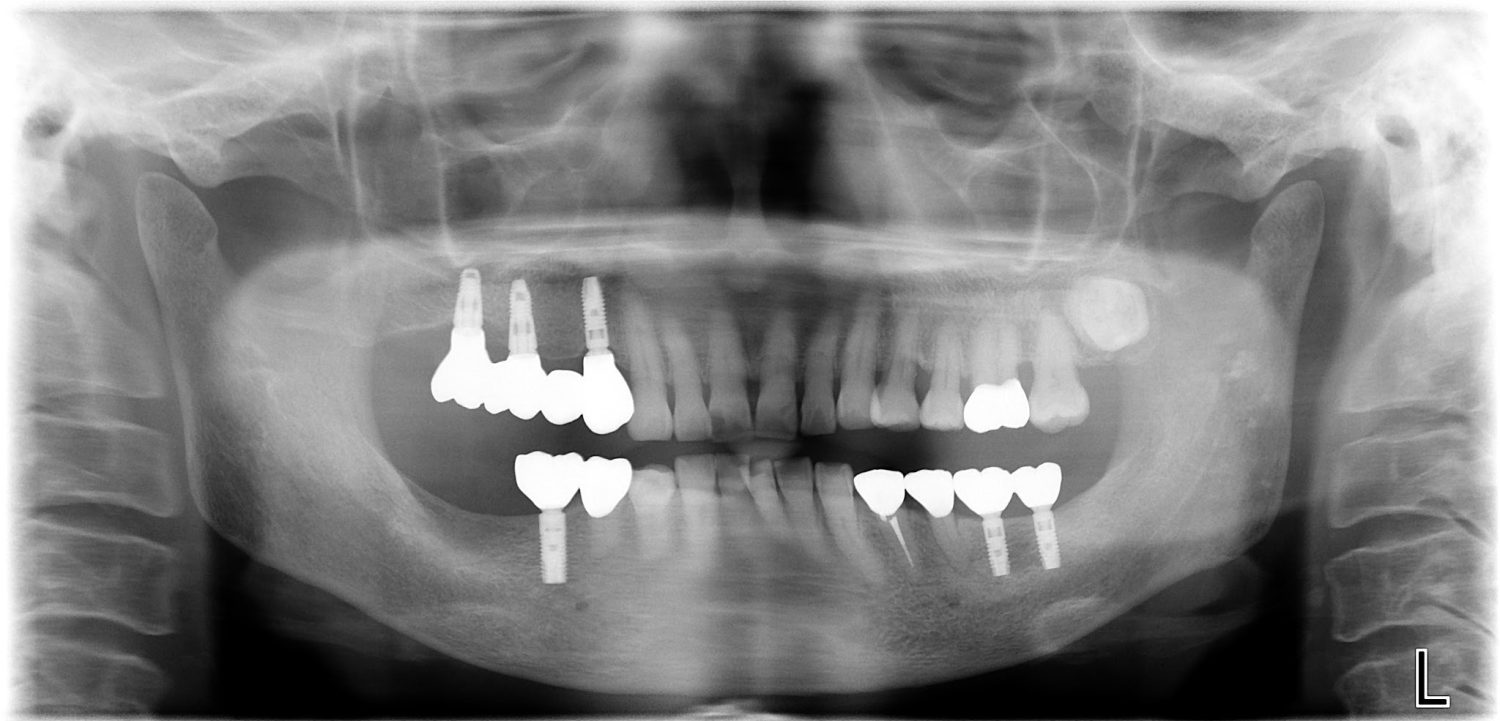

インプラント治療の症例紹介③

Before

After

主訴

むし歯の治療

治療内容

保存不可能な歯の抜歯

下顎にインプラント埋入し咬合再構成

治療費

2,688,400円(税込)

治療期間

14か月

治療回数

21回

想定されたリスク

※上部構造の形態が複雑になるため清掃が難しくなる。インプラント周囲炎の恐れがありました。

濱 仁隆先生

浜歯科

多数歯う蝕および多数歯欠損による咬合崩壊、保存不可能な歯の抜歯により上下無歯顎に。下顎に6本インプラント埋入する事で咬合再構成を行った。